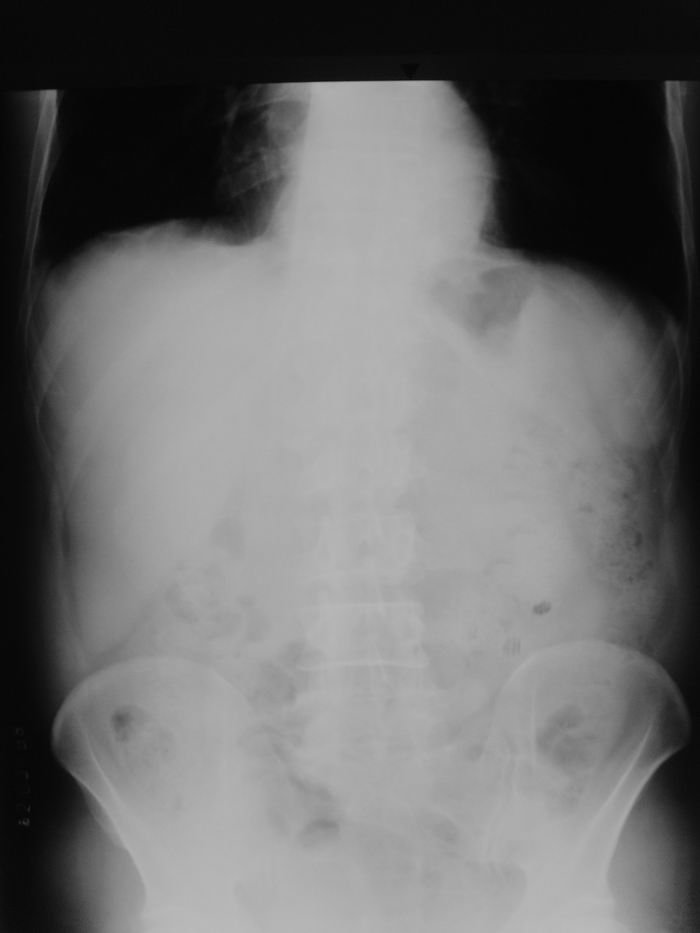

男性,47岁,车祸致胸痛2小时。

请大家看看后纵隔食道及降主动脉周围的软组织密度灶是什么?双侧膈肌脚内侧及椎管内的气体影是怎么回事?

伤者今天上午又来照了胸正斜位、立腹片、腰椎片: